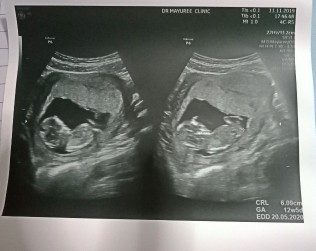

11 สัปดาห์ค่ะ 🥰

12 สัปดาห์ค่ะ